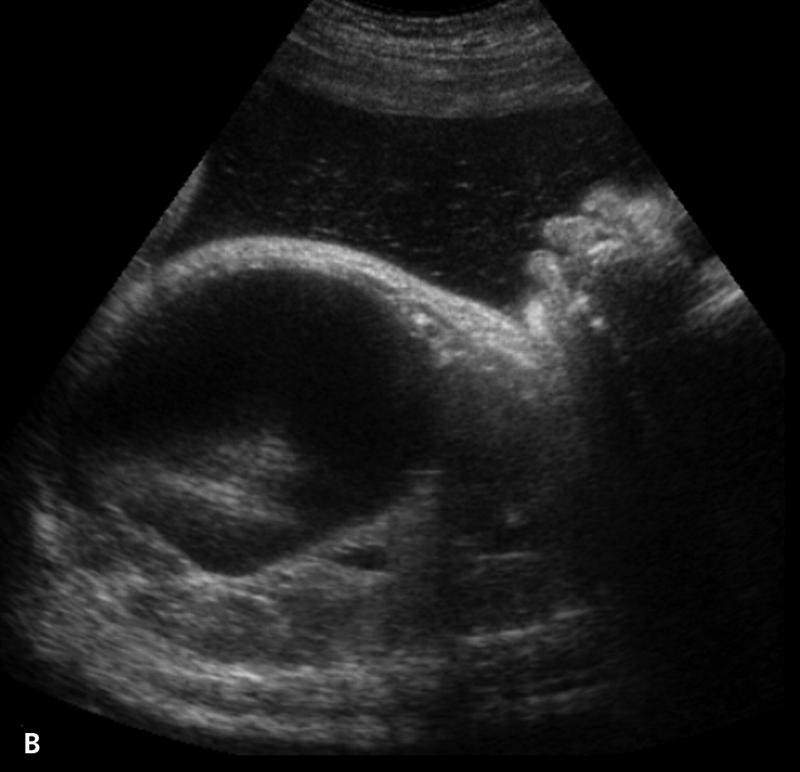

What is Polycystic liver disease?

This is an autosomal dominant genetic disease in which multiple small cysts cover the liver. 60% of patients with polycystic liver disease will have polycystic kidney disease.

What is the sonographic appearance of Polycystic liver disease?

Anechoic

Thin well-defined walls

Posterior

enhancement

Multiple

Varying in small size

What are the presenting symptoms of Polycystic liver disease?

abdominal pain

bloating or swelling in the abdomen

feeling full

What are the lab values that would suggest Polycystic liver disease?

↑WBC